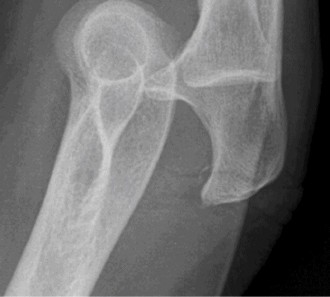

The correct answer is (A). The imaging demonstrates an axial CT scan with a large Hill–Sachs lesion. The lesion involves a large component of the humeral head (>40%) and as such is likely clinically significant. As the humerus is rotated externally the Hill–Sachs lesion is brought closer to the anterior rim of the glenoid and eventually engages the glenoid. Patients may perceive this as a painful click or locking episode. Lesions that involve 40% of the humeral head should be repaired to adequately address instability. The other answer choices all represent injuries that may be associated with a shoulder dislocation, although the large Hill–Sachs lesion is most responsible for his ongoing instability.

Hill–Sachs lesions are compression fractures of the posterosuperolateral

humeral head that occur when the head comes in contact with the glenoid during an acute anterior dislocation or after recurrent instability events. The relative incidence of these lesions is high, and it approaches 100% in patients with recurrent instability. It is important to understand that these lesions are bipolar—there is anterior glenoid damage in addition to the Hill–Sachs lesion; both of these must be addressed to optimize outcome. Lesions can be classified as engaging or nonengaging. Engaging lesions are oriented such that the long axis of the lesion is parallel to the anterior glenoid rim in the position of athletic function, i.e., abduction and external rotation. Engaging lesions tend to be more symptomatic, and instability may be associated with a sensation of catching or locking.